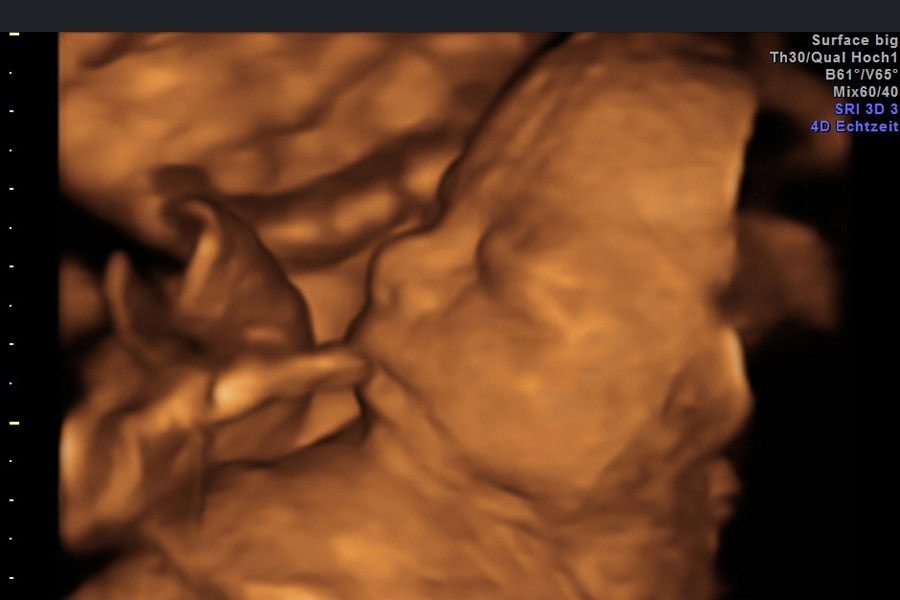

Die Feindiagnostik ist der herkömmlichen Ultraschalltechnik dank der 3D und 4D-Darstellung des Kindes im Mutterleib weit überlegen. Sie ermöglicht frühzeitige und genauere Befunde. Beurteilt werden die Organentwicklung, das Wachstum, die Fruchtwassermenge sowie die Lage und Aussehen der Plazenta und damit die Versorgung des Babys.